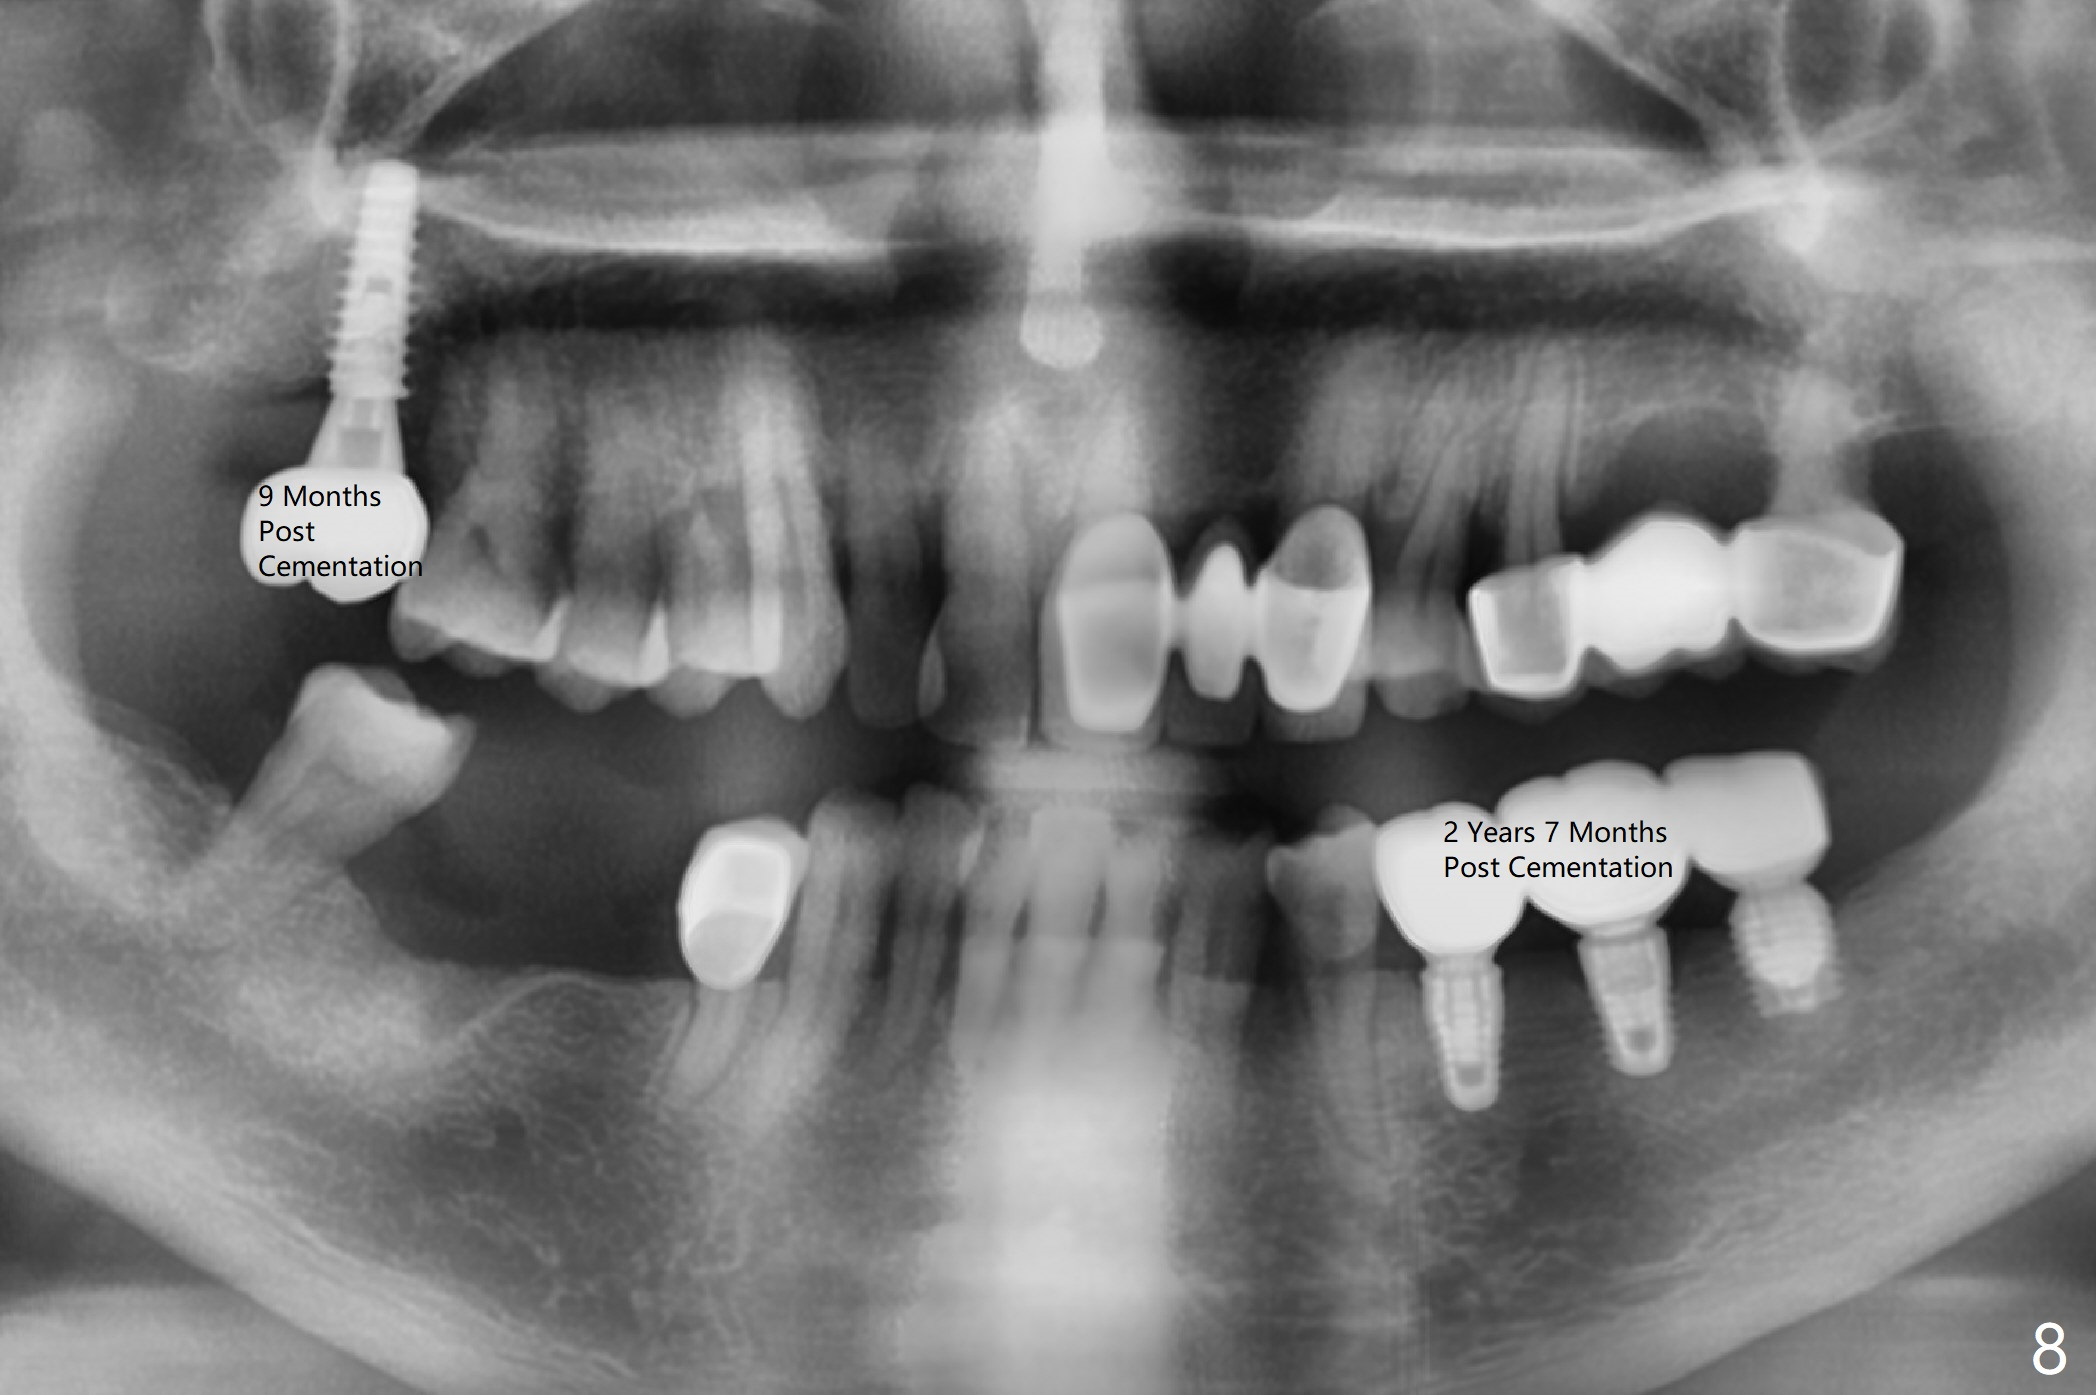

Five months post cementation, the patient returns because of loose abutment screw at #18. Bone resorption is noted (Fig.7 arrowheads). His oral hygiene is fair. He refuses implant at #2, saying that he dares not to chew on the left. When the screw became loose again 3 months later, he accepted the treatment. While he was returning to his home country, the lower right bridge was sectioned and the tooth #30 was removed. He is thinking of 2 implants at #29 and 30 (Fig.8). Bone loss appears not to get worse at #18-20 (Fig.9-11 (CBCT coronal sections, 2 years 7 months post cementation)). The implant at #19 is loose with a gap between the implant and the bone 3 years 5 months post cementation (Fig.12 *). SM implant does not last under stress (bruxism) and rigid implant/abutment connection.